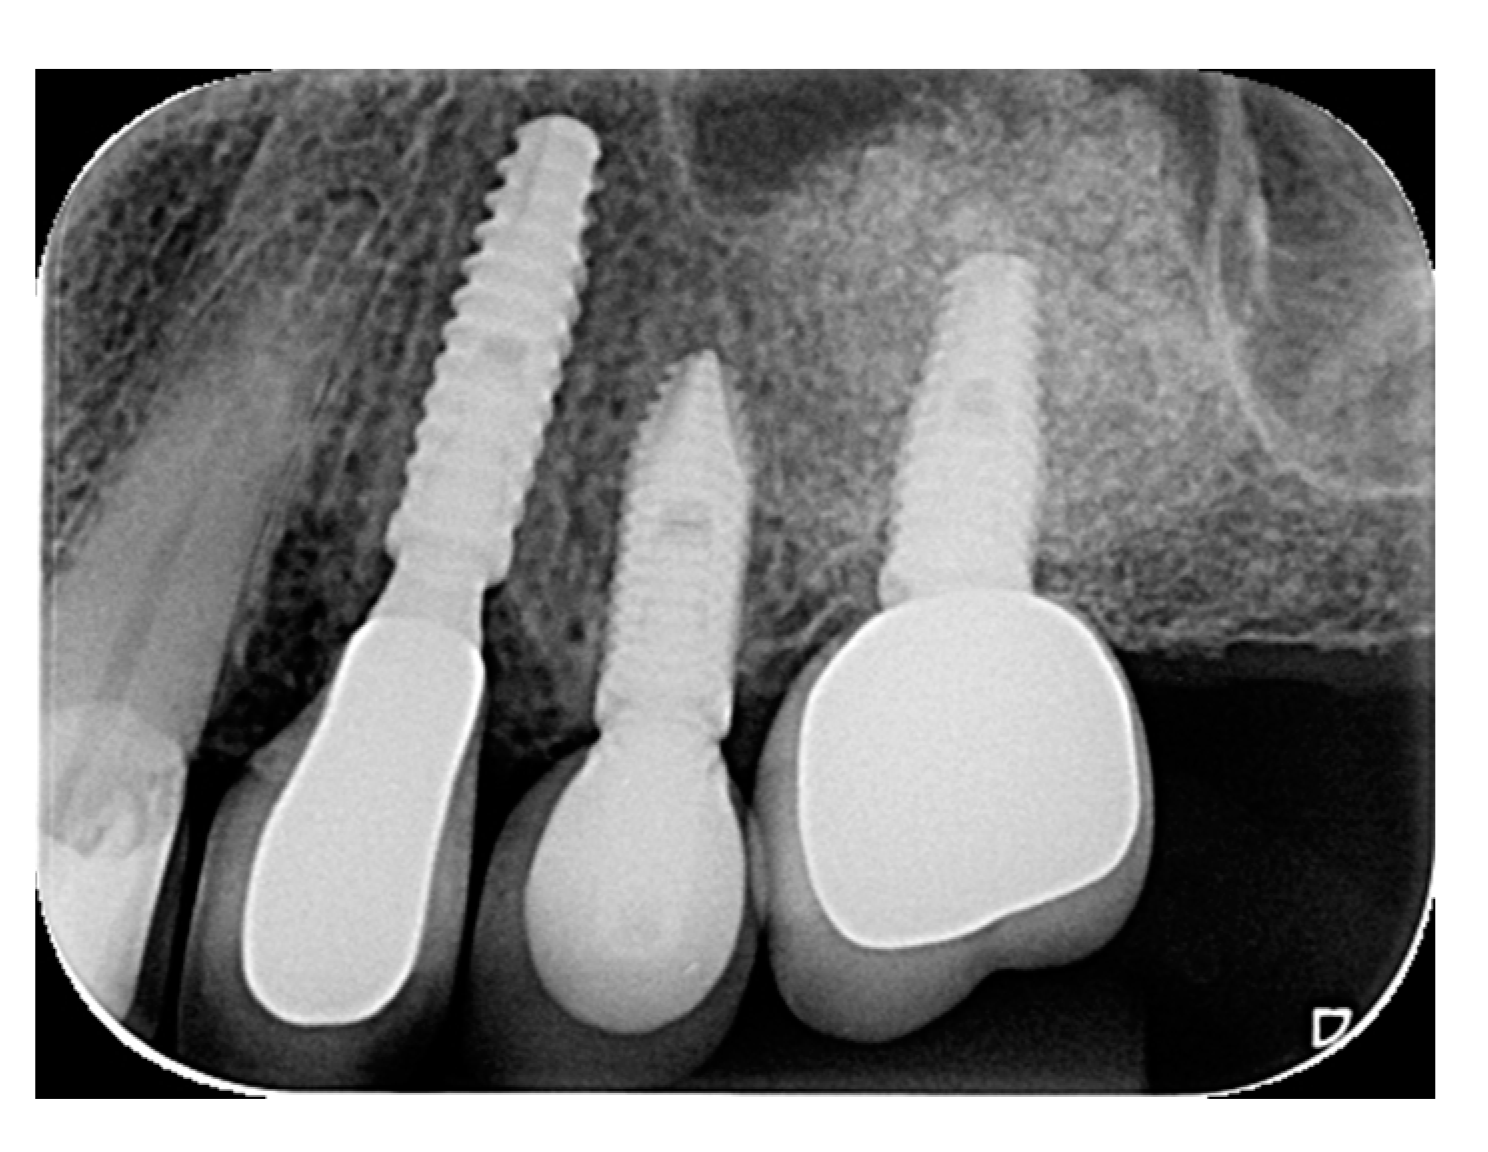

- Bleyan, S.; Gaspar, J.; Huwais, S.; Schwimer, C.; Mazor, Z.; Mendes, J.J.; Neiva, R. Molar Septum Expansion with Osseodensification for Immediate Implant Placement, Retrospective Multicenter Study with Up-to-5-Year Follow-Up, Introducing a New Molar Socket Classification. J. Funct. Biomater. 2021, 4, 66. [Google Scholar] [CrossRef] [PubMed]